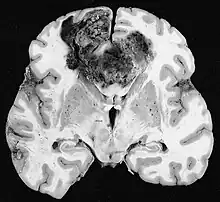

Clinically, VM is diagnosed through immunohistochemistry (IHC) and Periodic acid-Schiff stain (PAS) of patient tumor biopsy. IHC staining identifies the expression of common biomarkers of endothelial cells such as CD31, while PAS staining marks the extracellular matrix for glycoproteins, laminin, proteoglycans, heparin sulfate and collagens, which are known to be a sign of VM.[2] Clinicians diagnose a tumor as having VM by CD31-/PAS+ expressing blood conducting vessels, indicating that there are no endothelial cells but still vasculature present.[2][3]

Vascular mimicry may be divided into tubular and patterned matrix types.[9][3] Tubular VM is characterized by channels surrounded by glycoprotein covered tumor cells where endothelial cells would normally sit. Patterned matrix type VM lacks the endothelial-like tumor cells and is instead tumor cells that are enveloped by PAS+ matrix/